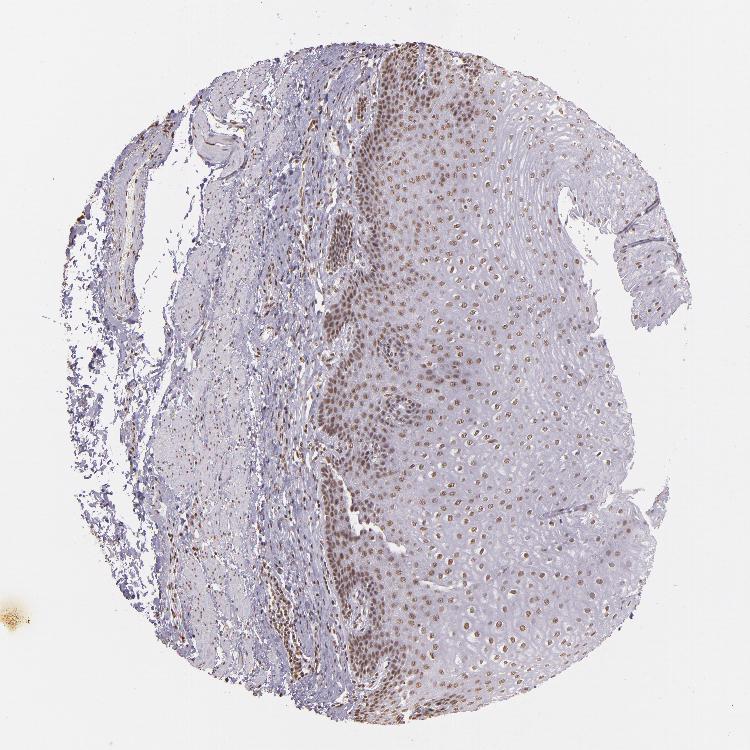

TISSUE PRIMARY DATA ESOPHAGUS Show tissue menu

Esophagus

ESOPHAGUS - Antibody stainingi

Antibody staining in the annotated cell types in the current human tissue is reported as not detected, low, medium, or high, based on conventional immunohistochemistry profiling in selected tissues. This score is based on the combination of the staining intensity and fraction of stained cells.

Each image is clickable and will lead to virtual microscopy that enables deeper exploration of all samples and also displays staining intensity scores, fraction scores and subcellular localization as well as patient and tissue information for each sample.

Antibody HPA036233Antibody CAB001480

Squamous epithelial cells MediumMedium